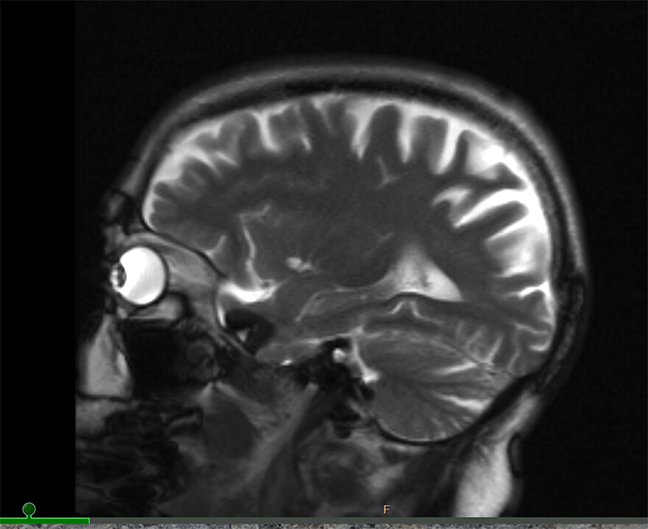

In 2023 I felt the need to address my concerns with memory (what’s your name again??) with brain scans and neurological testing. Not Alzheimers / dementia—the synapses simply aren’t firing like they used to.

Diagnosis: old operating system, no updates available!

June 2024 — I ended up in the emergency room again. Getting ready to go to bed the room started spinning, more intensely than adolescent memories of too much alcohol. Long story short: after an EKG, brain scan, and X-ray—to rule out a stroke—it was probably an inner ear thing — benign paroxysmal positional vertigo (BPPV)(you learn so many interesting names and acronyms) — possibly caused by my playful headshaking to some music earlier that evening; but who knows. Now that it has arrived it will likely return and so I am due for some physical therapy to help me deal with it. No more pogo-dancing in my future.